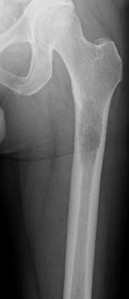

A 15-year-old male presents with deep knee pain awakening him at night. Radiographs show a permeative destructive lesion in the distal femoral metaphysis with a 'sunburst' periosteal reaction and Codman's triangle.

Biopsy confirms high-grade conventional osteosarcoma. What is the most critical prognostic factor for long-term overall survival in this patient?

Explanation

For localized high-grade osteosarcoma, the most important prognostic indicator is the histologic response to neoadjuvant chemotherapy. This is evaluated during the definitive resection. A 'good response' is typically defined as greater than 90% or 99% tumor necrosis. Patients who achieve this level of necrosis have a significantly improved disease-free and overall survival rate compared to 'poor responders' who have extensive viable tumor cells remaining.